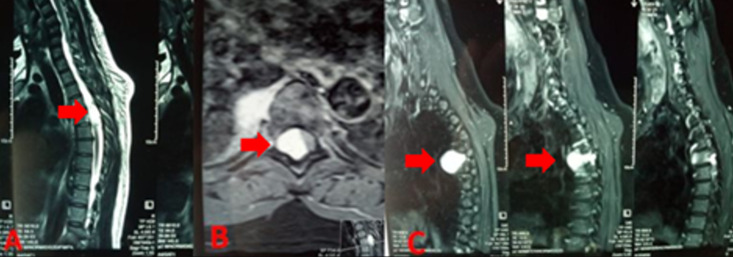

硬膜外海绵状血管瘤是一种罕见的血管畸形,占所有脊髓血管畸形的5-12%。我们报告一例由于海绵状血管瘤模仿沙漏形硬膜外神经瘤的临床和放射学特征而导致的D5-D6低位脊髓压迫。临床表现为进行性痉挛性截瘫超过6个月,患者41岁,无明显病史。磁共振成像显示D5-D6硬膜内压缩病变伴T2高信号,呈沙漏状,提示硬膜外神经瘤,伴显著的肛门外成分填充同侧椎体外侧间隙。免疫组化组织学检查证实为海绵状血管瘤。手术切除病灶后,术后结果良好。

Epidural cavernous hemangioma is a rare vascular malformation, accounting for 5-12% of all spinal cord vascular malformations. We report a case of low dorsal spinal cord compression at D5-D6 due to a cavernous hemangioma mimicking the clinical and radiological features of an epidural neuroma in an hourglass shape. The clinical presentation was progressive spastic paraplegia over six months in a 41-year-old patient with no significant medical history. Magnetic resonance imaging showed a compressive D5-D6 intradural lesion with T2 hyperintensity, displaying an hourglass appearance suggestive of an epidural neuroma, with a significant extracanal component filling the ipsilateral latero-vertebral space. Histological examination confirmed cavernous hemangioma by immunohistochemistry. The postoperative outcome was favorable following total surgical removal of the lesion.